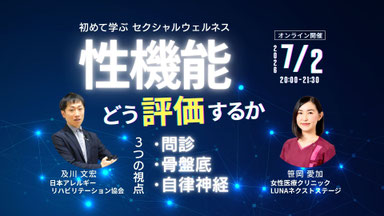

〜 セクシャルウェルネス理学療法シリーズ 〜

[理学療法士が関与できる「性」の領域とは]

第2回 性機能をどう評価するか[評価編]

『性交痛・挿入障害をどう評価するか』

― 問診と身体反応から骨盤底機能を読み解く ―

笹岡 愛加 先生(理学療法士)

『性機能と自律神経をどう評価するか』

― 問診と身体から捉える機能低下のサイン ―

及川 文宏 先生(理学療法士)